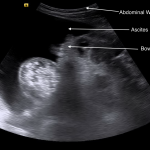

ABDOMINAL ULTRASOUND

Key features of ascites seen in this imaging modality are:

- Anechoic nature: ascites will allow sound waves to pass through it, so it will appear black/dark on ultrasound.

The gallery below organizes examples of how ascites will appear on abdominal ultrasound. Click on the thumbnails below to open up the gallery: